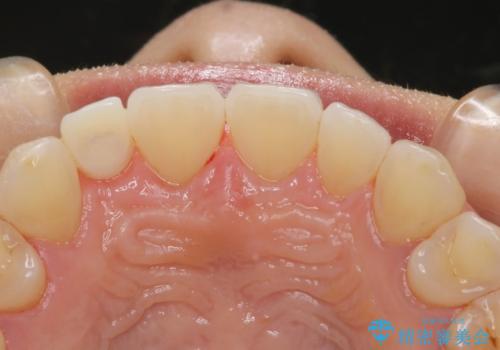

エアフローだけで歯が白くなったと喜んでいらっしゃいました。新しいマウスピースが届くまでの間はホームホワイトニングを行い歯の内部から白くしていきます。